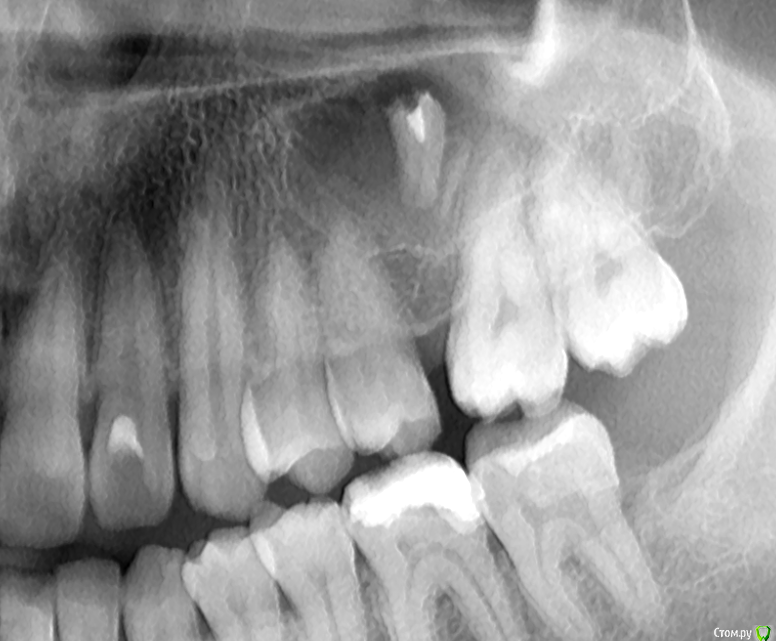

krokomot Опубликовано 5 октября, 2017 Поделиться Опубликовано 5 октября, 2017 http://http://s019.radikal.ru/i639/1710/da/f5e5ba37932d.pngканалы запломбированы до верхушек в 6-ом зубе, но вопросы к 7-ому 2 Ссылка на комментарий

Руслан81 Опубликовано 5 октября, 2017 Автор Поделиться Опубликовано 5 октября, 2017 каналы запломбированы до верхушек в 6-ом зубе, но вопросы к 7-ому а что с 7-м? Ссылка на комментарий

shishok Опубликовано 5 октября, 2017 Поделиться Опубликовано 5 октября, 2017 В дополнение:попросите своего стоматолога проверить 37 зуб(нижний крайний левый) на возможное наличие скрытой кариозной полости на передней поверхности(ближе к 36 зубу). Ссылка на комментарий

shishok Опубликовано 5 октября, 2017 Поделиться Опубликовано 5 октября, 2017 а что с 7-м? Близкое расположение пульпы к дну кариозной полости. 1 Ссылка на комментарий

DmitrySH Опубликовано 5 октября, 2017 Поделиться Опубликовано 5 октября, 2017 на снимке в посте №6 видна кариозная полость на передней поверхности зуба 37, на последнем снимке хуже видно Ссылка на комментарий